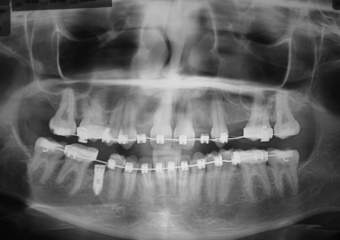

Raio X final com próteses em porcelana sobre implantes